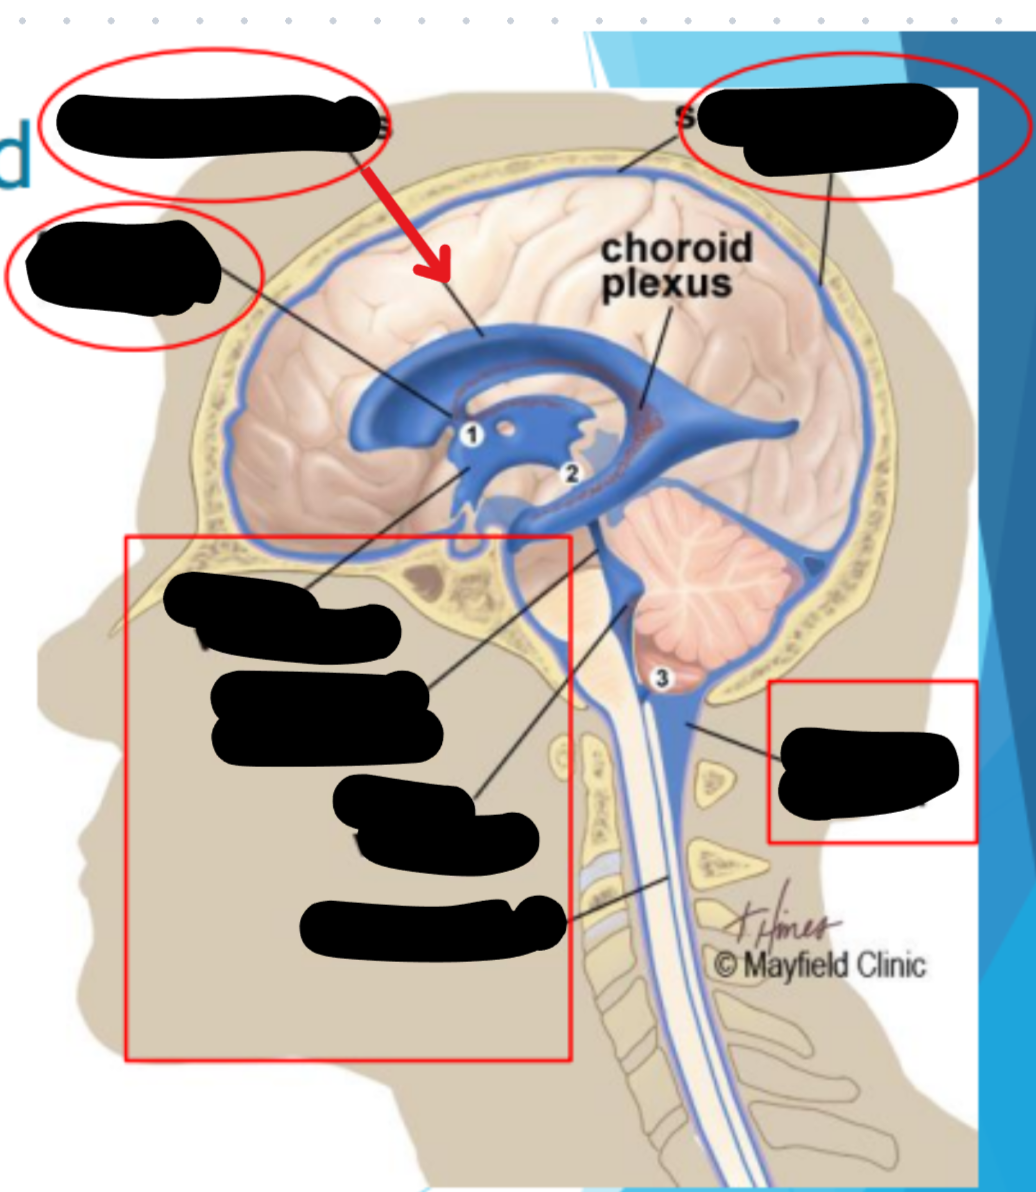

Ventricles

Hollow fluid-filled cavities

The ventricles contain the choroid plexus which creates CSF

37

New cards

Choroid plexus

Produces cerebrospinal fluid (CSF)

Maintains pressure in the brain

Cushions brain to prevent injury

38

term image

Ventricular system

39

Two lateral ventricles

40

Foramen of Monro

41

Third ventricle

42

Aqueduct of Sylvius

43

Lateral Horns

End in subarachnoid space

44

Central horn (connects inside spinal cord)

45

Fourth ventricle

46

Cycle of CSF

Lateral ventricles → Foramen of monro →Third ventricle → Aqueduct of sylvius → Fourth ventricle → Lateral horns + Central horn → Subarachnoid space (Brain and spine) → Arachnoid granulations (Absorb and recycle CSF) → Superior sagitall sinus → Jugular veins

47

Places where CSF flow can become obstructed

Obex